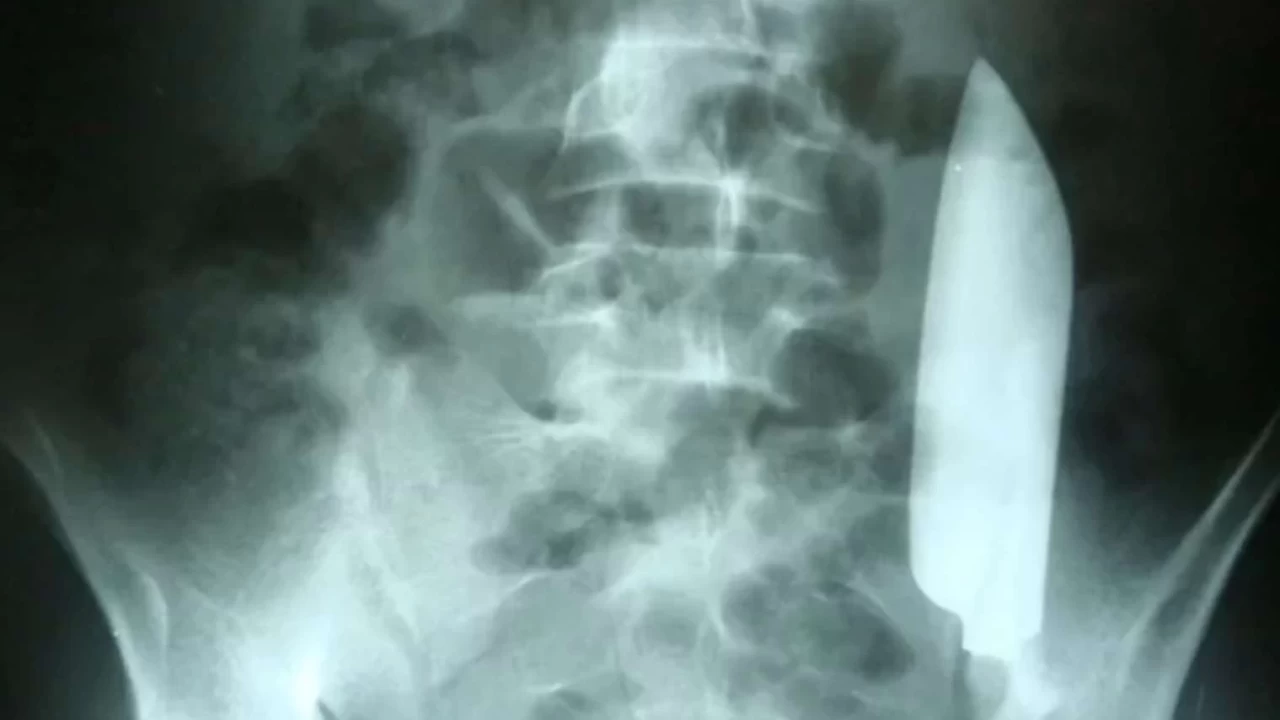

Şaşırtıcı Röntgen Sonuçları

Hastanede yapılan röntgen sonucunda doktorlar, 15 cm'lik bıçağın adamın karnında hala bulunduğunu ve sağdan sola doğru kaydığını tespit etti. En ilginç kısım ise, bıçağın iç organlara zarar vermemiş olmasıydı. Bıçak yaralarının genellikle ciddi kan kaybı ve enfeksiyon riskleri taşıdığı biliniyor, bu nedenle hastanın durumu oldukça kritik bir öneme sahipti.